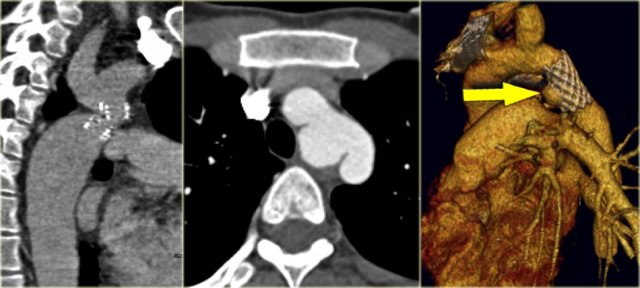

On the left a 2 month old boy with heart failure.

First study the image, then continue

The findings are:

• Large thymus which is normal for a 2 month old.

• Striking discrepancy between diameter of ascending and descending aorta.

The diagnosis is coarctation, which is nicely demonstrated on the posterior view of the reconstruction.

There are two types of coarctation.

The type we usually see is the post-ductal type, which is distal to the left subclavian artery.

The uncommon pre-ductal type is seen in neonates.

They present with severe heart failure, mostly within the first week of life, usually on the first day.

The occlusion is in front of the left subclavian.

First study the axial image followed by the sagittal reconstruction, then continue.

• Big internal mammarian arteries on the axial image due to a high grade stenosis as a result of a coarctation. Probably could not make the diagnosis based on the axial images alone.

• Post-ductal coartation only seen on sagittal reconstruction.

• Intercostal collaterals.

Pre-ductal type of coarctation Pre-ductal type of coarctation

On the left two neonates with the pre-ductal type of coarctation.

The stenosis is in front of the left subclavia and there is arch hypoplasia.

Collaterals do not occur, probably because they don't have time to develop.